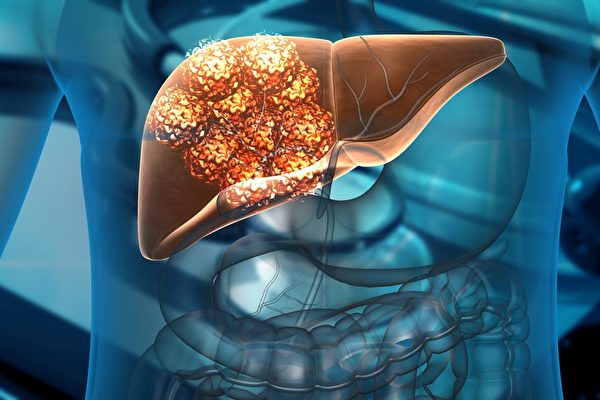

肝癌是美國發展最快的癌症死亡原因,每年奪走約3萬名美國成年人的生命。根據美國肝臟基金會的數據,自1980年以來,美國的肝癌死亡率增加了一倍以上,2000年至2016年間,肝癌死亡率激增了43%。

肝癌的形成

正常情況下人的細胞有一個正常的代謝過程,當細胞衰老死亡,新生的細胞就會替代它。癌症實際上是細胞發生癌變,造成生長失控,開始無止盡的分裂,同時失去正常細胞的功能,進而影響到身體器官的功能,最終導致人體死亡。

那麼人們常說的腫瘤和癌症是什麼關係?腫瘤分良性和惡性,惡性腫瘤就是癌症。癌症可以是有形的,比如細胞無止境分裂生長形成癌症腫塊,也有像白血病這樣由血液中某種白細胞癌變導致的血癌,沒有腫塊形成。

肝癌,尤其原發性肝癌是指肝細胞本身出現了癌變,生長失控,失去了正常肝細胞應有的功能,損害了肝臟的功能,最後使肝功能衰竭導致死亡。

肝癌是比較凶險的癌症之一,它的死亡率高是因為肝癌早期並無明顯症狀。若出現症狀,肝癌已是較晚期,並且很多情況下癌症已經轉移,通常轉移到附近的膽囊及和它相臨近的器官,還會通過血液和淋巴系統轉移到骨頭上、肺上,甚至轉移到腦部等等。

肝癌病人在早期往往出現疲勞、食慾下降、體重下降;比較嚴重時期會出現小便深色、皮膚和眼睛出現黃疸,進而腹部產生包塊。

肝臟位於腹部右側,在右側肋骨的下緣背後。如果肝臟出現腫瘤,它會腫大,在體檢的時候能夠摸到腫大的肝臟,甚至能摸到肝臟上的包塊,這時能觀察到腹部明顯的腫大。更嚴重的肝癌會有大量腹水產生,還會導致肝腦綜合症,使病人昏迷等。